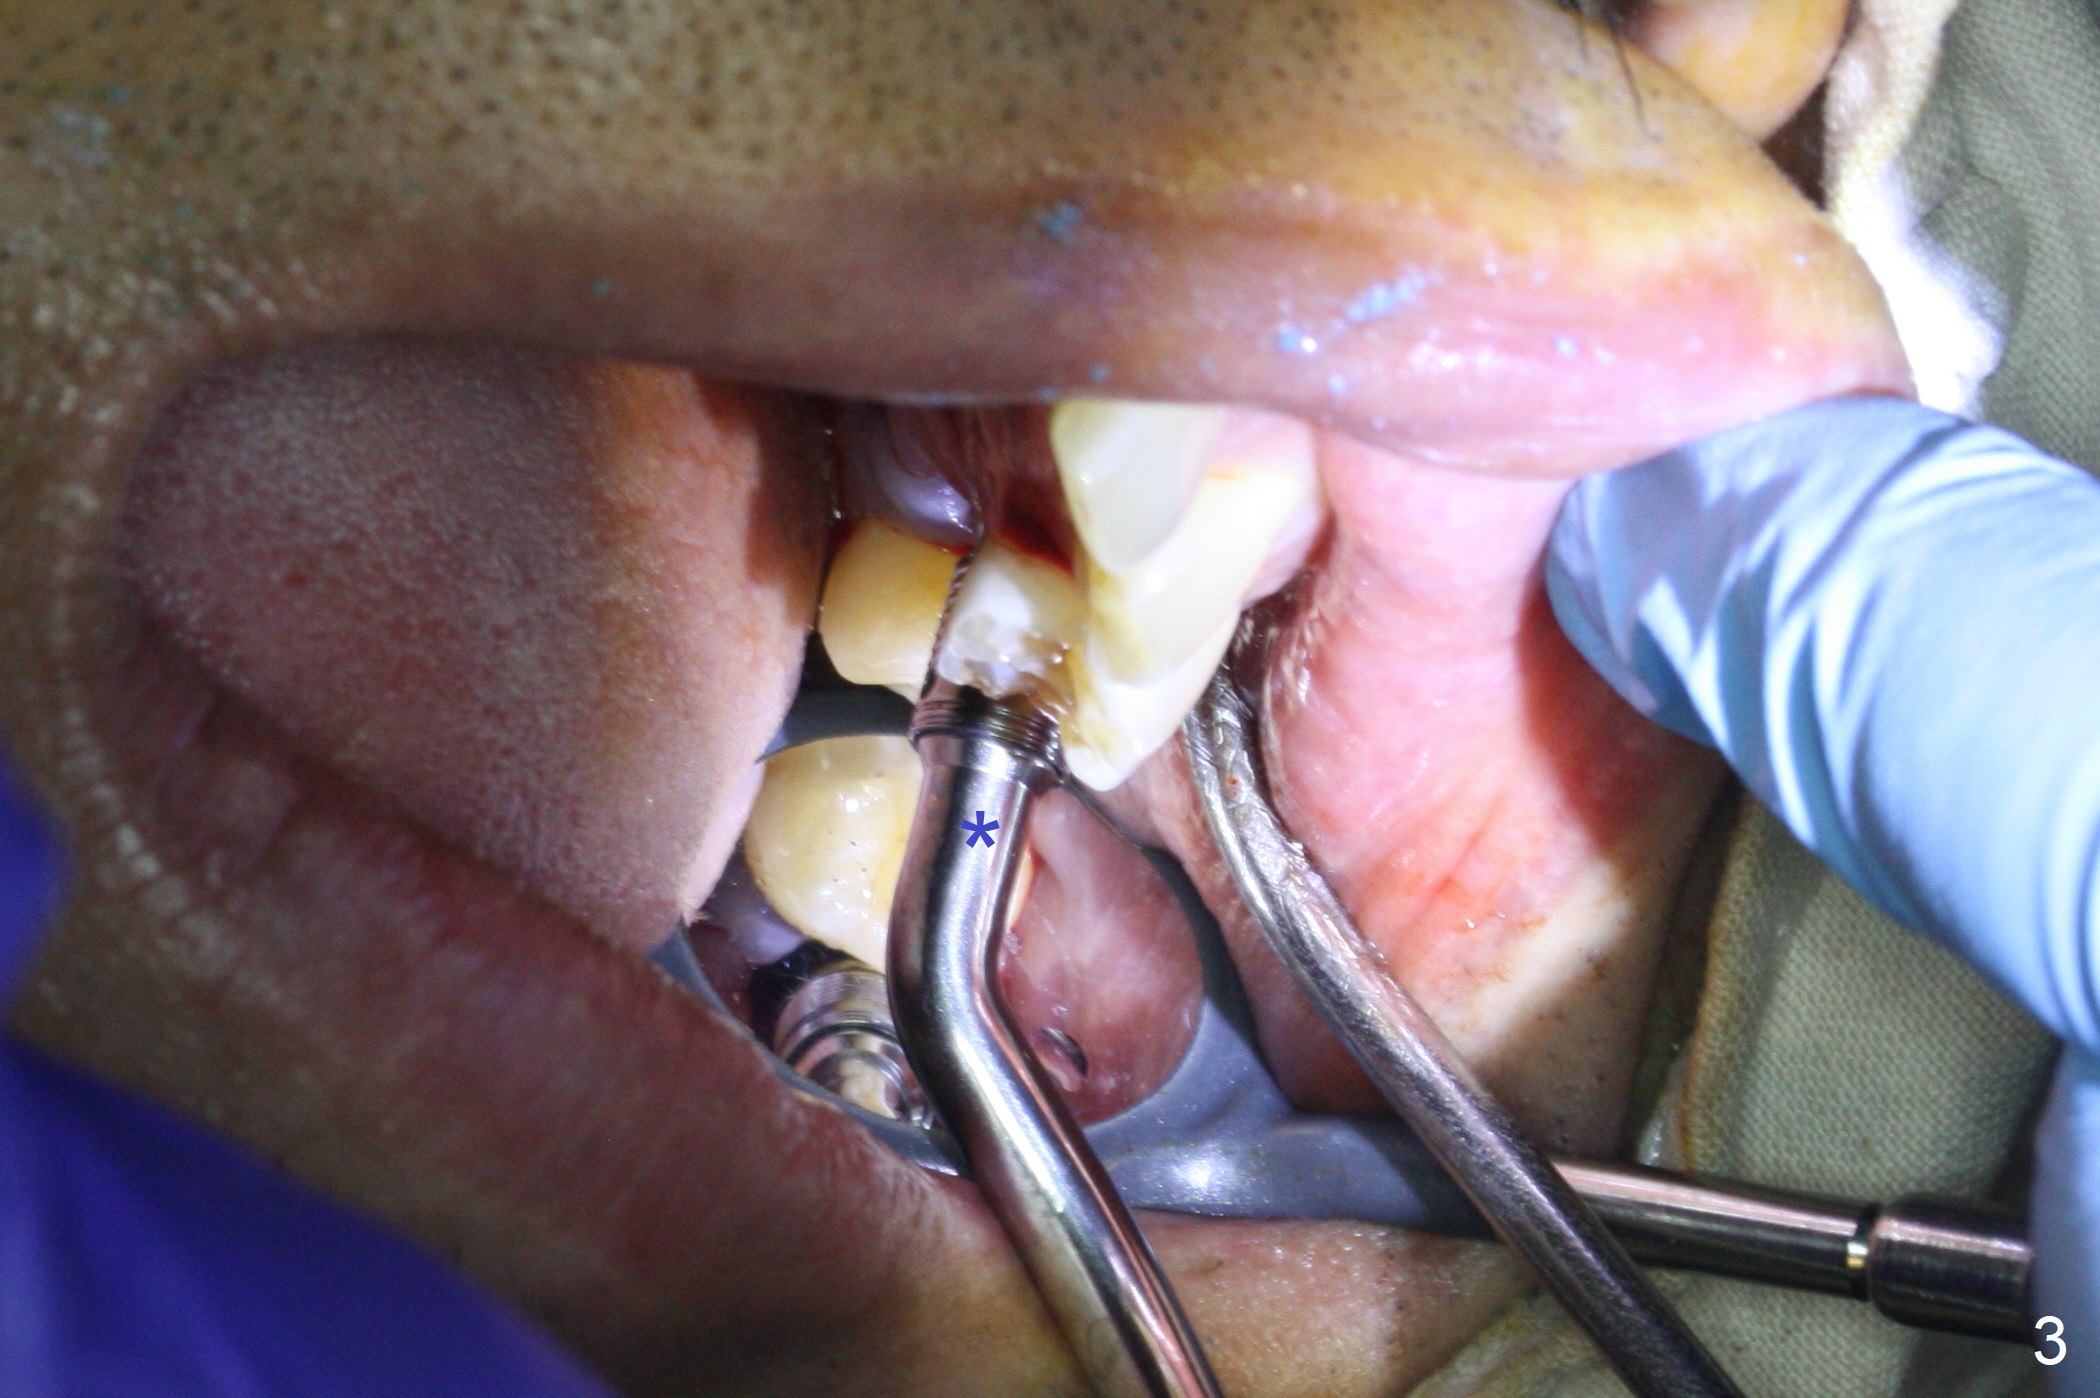

When the displaced tooth #14 (Fig.1) with palatal gingival recession (Fig.2) is extracted, the buccal plate is low, while the palatal one is lost.  Osteotomy is initiated in the bottom of the large socket with Marking Drill.  The bone turns bluish, suggesting thin bone (in fact less than 1 mm as well as low density).  Magic Sinus Lifter (Fig.3 *, Fig.4 blue area) is used for sinus lift (Fig.4 (red curved line: lifted sinus membrane; grey area: a portion of the lifted sinus floor), followed by insertion of a piece of PRF plug and Vanilla bone graft for sinus lift.  The osteotomy is enlarged lightly with 4.8 mm Magic Drill (compare black strips between Fig.4,5).  A 5x9 mm dummy implant (Fig.5 green) is dislodged into the sinus.  The lifted sinus membrane holds the implant in place.  The black thin strip in Fig.5 and black circle in Fig.6a (occlusal view) represents the osteotomy.  After increase in the osteotomy with Lindamann bur (Fig.6b red circle), the implant (Fig.6c green) is retrieved with endodontic forceps (Fig.6c two blue dots (beaks of the forceps); Fig.7,8).  With the enlarged osteotomy (Fig.6d), a 6x9 mm dummy implant is placed deep (Fig.9).  The definitive implant is 6.5x11 mm with insertion torque ~ 15 Ncm (Fig.10).  With placement of a healing screw and further placement of allograft (Fig.11 *), the socket is closed with PRF membrane and collagen plug (Fig.12).